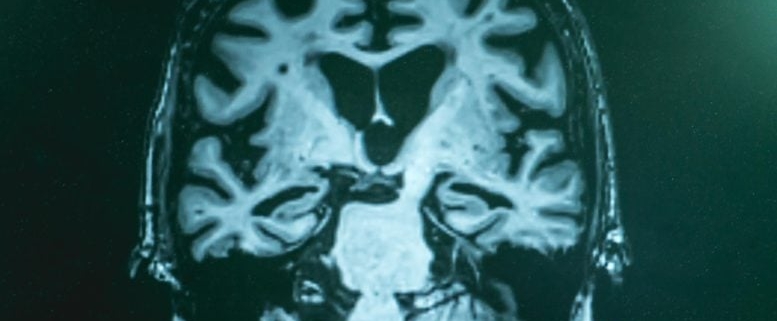

A groundbreaking new imaging technique is shining an unprecedented light on the molecular landscape of Alzheimer’s disease, offering researchers a brain-wide “chemical map” that could transform how we understand, diagnose, and ultimately treat this devastating neurodegenerative condition.

In a landmark study, scientists at Rice University have unveiled what they describe as the first comprehensive, label-free molecular atlas of an Alzheimer’s-affected brain in an animal model. This pioneering work moves far beyond the traditional focus on amyloid plaques—those infamous protein clumps long considered the hallmark of Alzheimer’s—and instead captures a broader, more intricate chemical portrait of the disease.

By using SRH, the Rice team was able to generate a detailed, three-dimensional chemical map of the entire mouse brain affected by Alzheimer’s. This map reveals not just the location of amyloid plaques, but also the distribution of lipids, proteins, and other biomolecules that play crucial roles in brain health and disease. In essence, it provides a panoramic view of the molecular chaos that underlies Alzheimer’s, highlighting disruptions that were previously invisible to researchers.